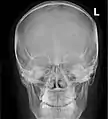

![]() Paranasal sinuses seen in a frontal view | |

Paranasal sinuses are a group of four paired air-filled spaces that surround the nasal cavity.[1] The maxillary sinuses are located under the eyes; the frontal sinuses are above the eyes; the ethmoidal sinuses are between the eyes and the sphenoidal sinuses are behind the eyes. The sinuses are named for the facial bones and sphenoid bone in which they are located. Their role is disputed and no function has been confirmed.

Humans possess four pairs of paranasal sinuses, divided into subgroups that are named according to the bones within which the sinuses lie. They are all innervated by branches of the trigeminal nerve (CN V).

- The maxillary sinuses, the largest of the paranasal sinuses, are under the eyes, in the maxillary bones (open in the back of the semilunar hiatus of the nose). They are innervated by the maxillary nerve (CN V2).[2]

- The frontal sinuses, superior to the eyes, in the frontal bone, which forms the hard part of the forehead. They are innervated by the ophthalmic nerve (CN V1).[2]

- The ethmoidal sinuses, which are formed from several discrete air cells within the ethmoid bone between the nose and the eyes. They are innervated by the ethmoidal nerves, which branch from the nasociliary nerve of the ophthalmic nerve (CN V1).

- The sphenoidal sinuses, in the sphenoid bone. They are innervated by the ophthalmic and maxillary nerve (CN V1 and V2).[2]